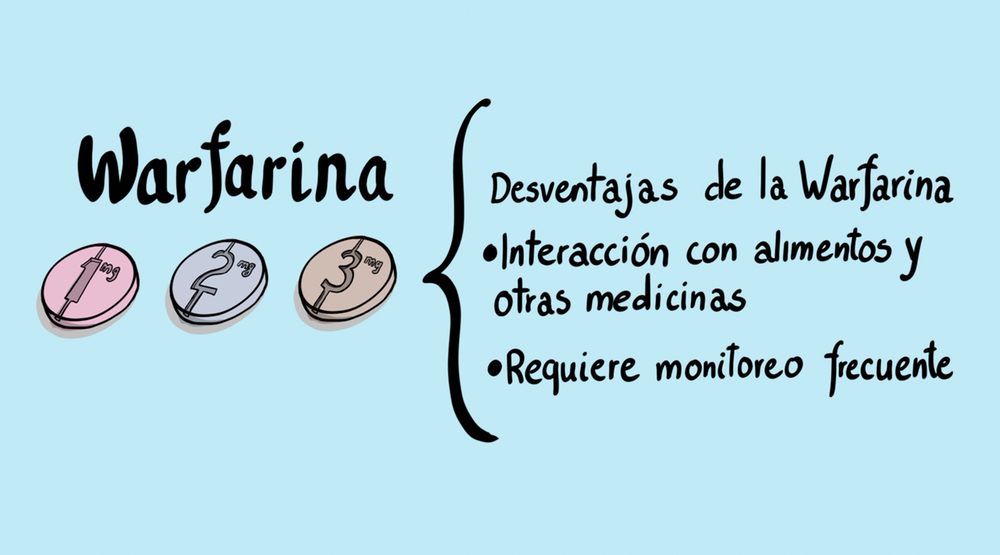

Hasta hace poco, la Cumadina era la única opción de anticoagulante disponible para pacientes con F.A.para prevenir un derreme cerebral. La Cumadina puede proteger de un derrame pero es una droga muy difícil de tomar ya que requiere pruebas frecuentes. Afortunadamente, ya hay cuatro anticoagulantes orales nuevos que no necesitan pruebas de sangre frecuentes para el monitoreo y que tienen leves interacciones con la comida y otros medicamentos.